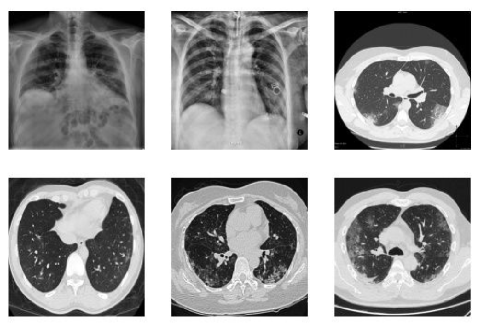

During the testing phase, several standard datasets like Set5 [41], Set14 [42], BSDS100 [43] and Urban100 [44] have been utilized to evaluate the performance of the proposed architecture. The metrics used for image quality assessment are PSNR and SSIM [45]. Few published methods work with larger datasets like DIV2K [11], ImageNet[46] and MS-COCO[47]. However, our choice of datasets for comparison has been used to keep it consistent with the majority of the methods that make use of it. The above datasets used for testing mainly consist of natural images. As pointed out earlier, transfer learning is carried out on the proposed architecture, which is now tested on medical images. For this, COVID-19 image database which contains a set of images collected by Cohen [48] are used. The dataset contains of chest X-ray and computed tomography (CT) images. The images are mainly in gray-scale format and is a collection of anterior-posterior view of chest X-rays. The dataset is continuously updated and it is worth mentioning that the resolution of images varies from image to image. A sample of these images can be found in Fig. 6.

Next, SR results on COVID-19 medical images is carried out. Here, the aim is not to detect the infection of COVID-19 through images, but to enhance the quality of these image to provide better diagnosis. The dataset used for this purpose is presented in Cohen [48]. As our model is trained on single channel, i.e. Y(luminance) and medical images are gray-scale image that contains only luminance information of the pixel and no color information. This provides a flexibly to use TTDSR architecture on medical images using transfer learning. The SR results on the image can be seen in Fig.9. The average PSNR and SSIM comparison on COVID-19 dataset can be seen in Table III. It can be observed that the proposed method gives better results compared to other methods.